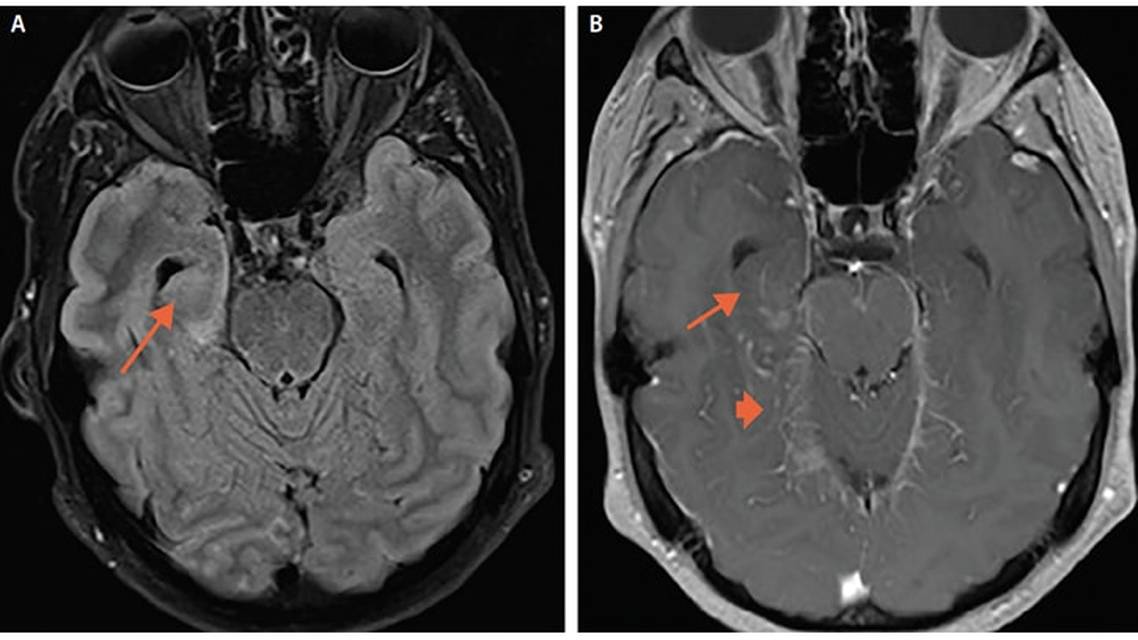

Upon admission to the hospital, Mr. L was febrile (101.3°F) and mildly encephalopathic (alert and oriented to the family at bedside, as well as to the month and year, but not to his location). He had no nuchal rigidity or focal neurologic signs on examination. Results of routine laboratory testing showed peripheral leukocytosis (21 x 103/mcL with 89% neutrophils), and elevated C-reactive protein (CRP; 11.2 mg/L). Cerebrospinal fluid (CSF) analysis revealed marked lymphocyte-predominant pleocytosis (401 leukocytes/mL, 68% lymphocytes, 6% neutrophils), elevated protein (94 mg/dL), and normal glucose. Results of a meningoencephalitis CSF panel were negative, and extensive infectious workup to evaluate for bacterial, mycobacterial, viral, fungal, and spirochetal infections were unrevealing. A CSF sample was sent to be tested for autoimmune encephalitis; however, the result was not available until after Mr. L’s discharge. Brain MRI findings showed a small region of right temporal lobe enhancement with leptomeningeal enhancement and cortical edema as well as ill-defined enhancement along the upper brainstem (Figure 1). Prolonged videoEEG results revealed right temporal slowing without epileptiform activity.

During a scheduled follow-up visit to the neurology clinic 3 weeks after discharge, Mr. L reported new symptoms: bilateral blurred vision, numbness on the left side of his face and tongue, loss of taste on the left side of his tongue, and recurrence of headache. On fundoscopic examination, optic nerve swelling was seen bilaterally, more on the right than on the left. Mr. L was referred to the emergency department and readmitted to the neurology service. Upon admission, he was afebrile, hemodynamically stable, and had a normal mental status examination. Significant findings of his neurologic examination included an area of central scotoma in the right eye, visual acuity 20/800 on the right and 20/40 on the left, horizontal diplopia with nystagmus on both right and left end gaze, diminished sensation in the left V3 distribution, and global pathologic hyperreflexia with preserved strength. Repeat CSF analysis results showed elevated opening pressure of 23 cm H2O, normal cell count and glucose, persistently elevated protein (94 mg/dL), and a negative meningoencephalitis panel. Brain MRI findings showed new, irregularly enhancing lesions in the posterior mesial temporal lobes, subcortical cerebral hemispheres, bilateral middle cerebellar peduncles and left cerebellum, as well as enhancement of the optic nerves and optic nerve sheathes bilaterally (Figure 2A-C). Spine MRI revealed small enhancing lesions in the cervical and thoracic spinal cord (Figure 2D).